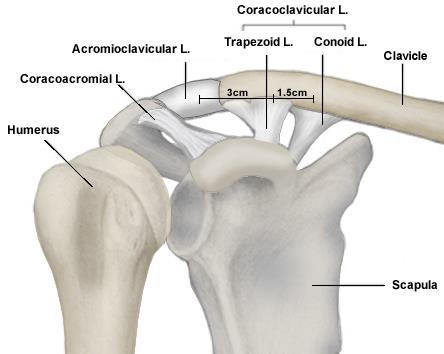

كسور نهاية الترقوة البعيدة هي إصابات شائعة تصيب الكتف، وغالبًا ما تحدث نتيجة السقوط أو الإصابة المباشرة. يعتمد أفضل عل…